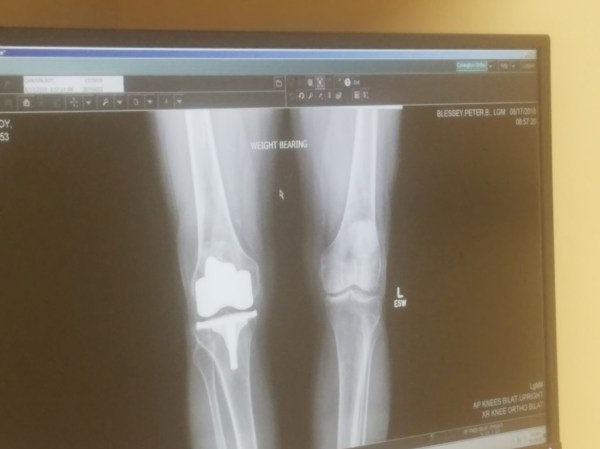

I had partial knee replacement surgery done by Dr. Peter Blessey. The surgery went great and the recovery was smooth.